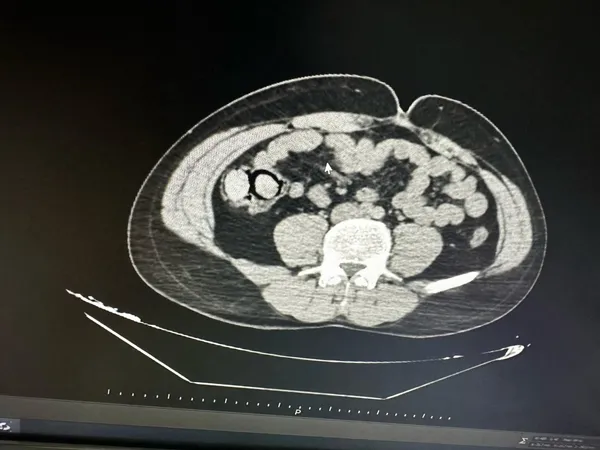

Narkotik Suçlarla Mücadele Şube Müdürlüğüne bağlı narkotik zamanları, otobüslerle ilimize gelen iki şüpheli şahsı gözaltına aldı. Yapılan iç beden muayenesinde, şüphelilerin midesinde toplam 113 gram metamfetamin maddesi ele geçirildi.